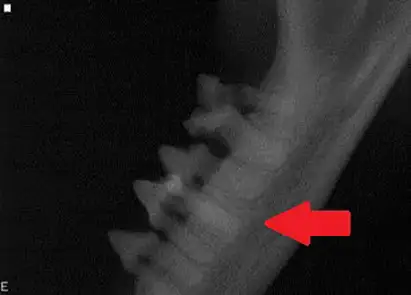

Dental radiograph of the left mandibular premolar teeth in a dog showing a classic example of canine tooth resorption.

Diagnosis: When tooth resorption (TR) is seen on routine dental radiographs, the next step is to carefully evaluate the tooth with a dental explorer along the gingival margin and look for clinical evidence of resorption (a sticky or rough area at or just below the gum line).

Treatment: If clinical evidence of resorption is found, the tooth should be extracted. If there is no clinical evidence of a lesion, radiographic monitoring is acceptable, as root resorption is reported to be non-painful in humans.

Extractions of these teeth can be challenging due to the high degree of ankyloses and resorption, and referral to a veterinary dentist is strongly recommended. Crown amputation is not a recognized treatment for these lesions; however, the first premolar tooth (red arrow) may be a candidate, as the end of the root appears isolated from the rest of the tooth and completely surrounded by new bone.